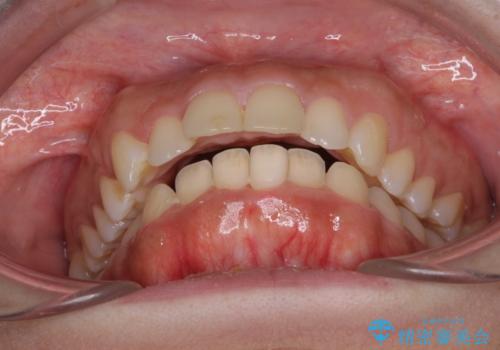

- 口元の突出感と口の閉じにくさを気にして来院された患者様です。

上下左右の小臼歯4本を抜歯し、ワイヤー装置にて口元を引っ込めるよう矯正治療を行うこととしました。

上下顎ともに前突しており、特に上顎は著しい突出感でした。

また、下顎歯列には左右差があり、非対称な抜歯が必要と判断されたため、治療は困難なものとなりました。